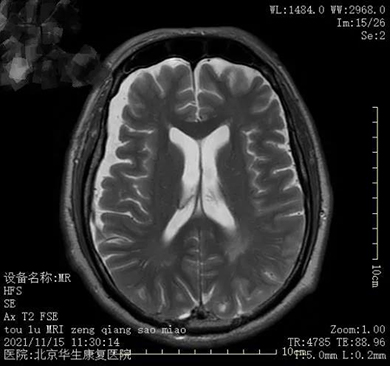

【神经康复科病例分享】脑出血康复

本期为大家分享的是:脑出血康复,欢迎阅读、分享!